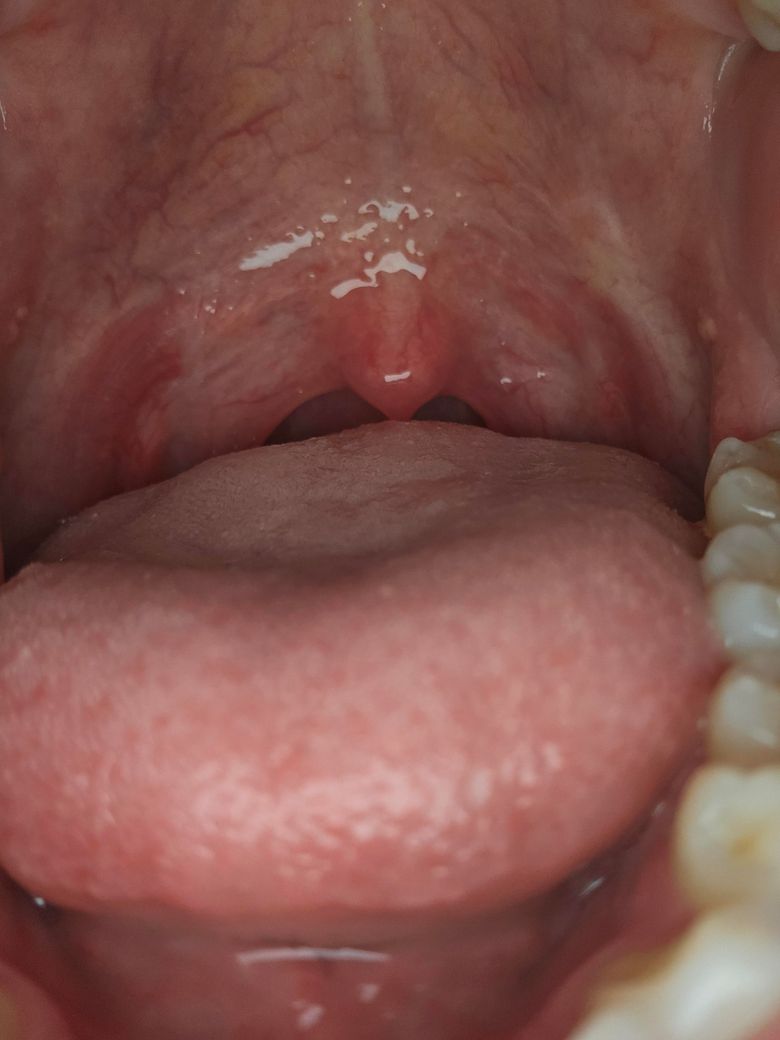

동네 치과랑 이비인후과에서도 잘 모르겠다는데이게 뭘까요??

약 2주전 감기에 걸려서 입속을 확인하니 편도쪽(양 옆 볼쪽)에 하얀 알갱이 같은게 생겼는데

확실한건 편도결석은 아니에요

근데 2주나 지났는데 없어지지 않는데

치과랑 이비인후과에서도 모르겠대요

괜찮을거라고만 하시는데...

통증같은건 없어요

감기 후에 편도 부위에 하얀 알갱이 같은 것이 나타났다는 증상은 여러 가지 원인으로 발생할 수 있습니다. 우선, 편도결석이 아니라면 편도염의 일종일 가능성도 있어요. 감기나 다른 상기도 감염 후에 편도선에 염증이 생기면서 작은 하얀 알갱이나 고름 덩어리가 생길 수 있습니다.

이 알갱이는 때때로 편도선에 쌓인 세균, 각질, 죽은 세포 등이 혼합된 것이며, 일반적으로 통증 없이 발생할 수 있어요

하지만 통증이 없고 시간이 지나도 증상이 지속된다면 편도선의 염증이나 불완전한 회복일 수도 있으며, 이는 자연적으로 해결될 수 있지만 시간이 오래 걸릴 수 있습니다. 만약 계속해서 하얀 알갱이가 사라지지 않거나 다른 증상이 생긴다면, 다시 한 번 이비인후과에서 추가적인 검사(편도 초음파나 세균 배양검사 등)를 받아보는 것이 좋습니다.